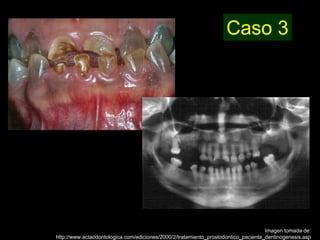

Dentinogénesis imperfecta es una condición genética que causa un disturbio en la formación de la dentina. Existen tres tipos principales. El tipo I se asocia con osteogénesis imperfecta. El tipo II solo afecta la dentina y causa dientes amarillos o grises con atrición. El tipo III es raro y se encuentra en un área aislada de Maryland, con exposiciones pulpares frecuentes. Todos los tipos muestran características radiográficas como obliteración de cámaras y conductos,